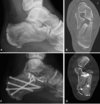

How are calcaneal fractures classified and how do they occur?

Most commonly fractured tarsal bone usually due to axial loading (fall from height). Associated with other fractures

Intrarticular (75%)

Articular surface of subtalar joint, further classified by Sanders Classification. Intra need definitive fixation

Extraarticular (25%)

Avulsion fractures, usually calcaneal tuberosity by Achilles tendon

How do calcaneal fractures present?

- Recent trauma

- Pain and tenderness around calcaneal region

- Inability to weight bear

- Swollen and bruised

- Shortened and widened heel

- Varus deformity

- Assess posterior heel skin integrity (any tenting or blanching needs emergency surgical intervention)

What investigations should you do if you suspect a calcaneal fracture?

- Gold standard CT

- Plain film radiograph (AP, lateral, oblique): will show calcaneal shortening, varus tuberosity deformity, decreased Bohler’s angle

Can do MRI

How are calcaneal fractures managed?

Conservative (<2mm displacement or normal Bohler’s angle)

- Cast immobilisation and no weight bearing for 10-12 weeks

Surgical

- Closed reduction with percutaneous pinning if large fracture but minimal displacement

- ORIF otherwise

- Emergency surgical fixation if any skin compromise